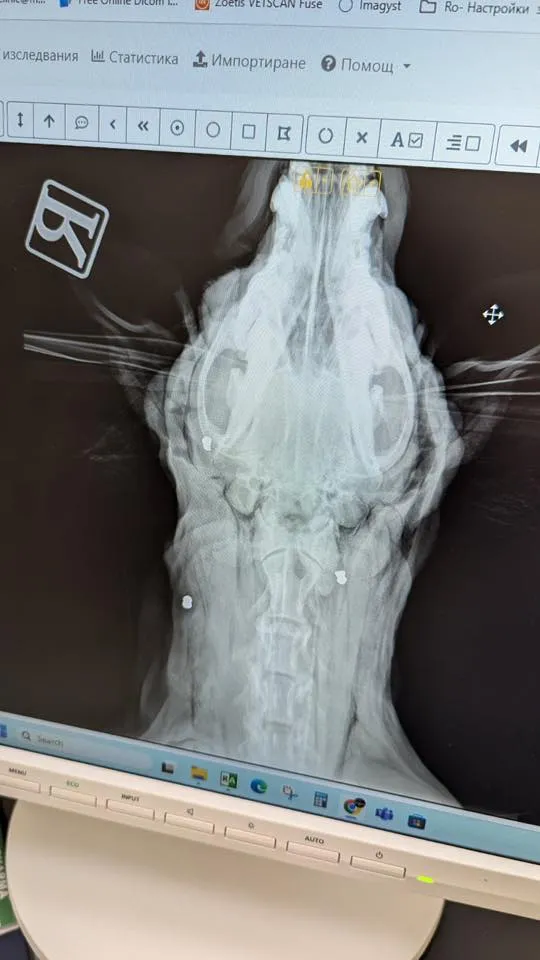

Животното е било транспортирано по спешност в ветеринарна клиника, където лекарите установяват осем прострелни рани от въздушна пушка – една от тях в окото и друга в трахеята. Последната е застрашавала живота ѝ и се е наложила незабавна операция.

Само за първия ден сумата за лечението, операцията и прегледите е достигнала 1600 лв., а предстоят още сериозни разходи – медикаменти, контролни изследвания, рентгенови снимки, престой в клиниката и рехабилитация.